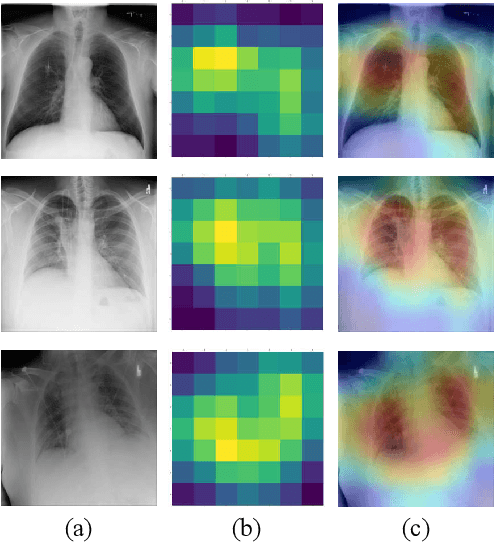

Abstract:The COVID-19 disease was first discovered in Wuhan, China, and spread quickly worldwide. After the COVID-19 pandemic, many researchers have begun to identify a way to diagnose the COVID-19 using chest X-ray images. The early diagnosis of this disease can significantly impact the treatment process. In this article, we propose a new technique that is faster and more accurate than the other methods reported in the literature. The proposed method uses a combination of DenseNet169 and MobileNet Deep Neural Networks to extract the features of the patient's X-ray images. Using the univariate feature selection algorithm, we refined the features for the most important ones. Then we applied the selected features as input to the LightGBM (Light Gradient Boosting Machine) algorithm for classification. To assess the effectiveness of the proposed method, the ChestX-ray8 dataset, which includes 1125 X-ray images of the patient's chest, was used. The proposed method achieved 98.54% and 91.11% accuracies in the two-class (COVID-19, Healthy) and multi-class (COVID-19, Healthy, Pneumonia) classification problems, respectively. It is worth mentioning that we have used Gradient-weighted Class Activation Mapping (Grad-CAM) for further analysis.